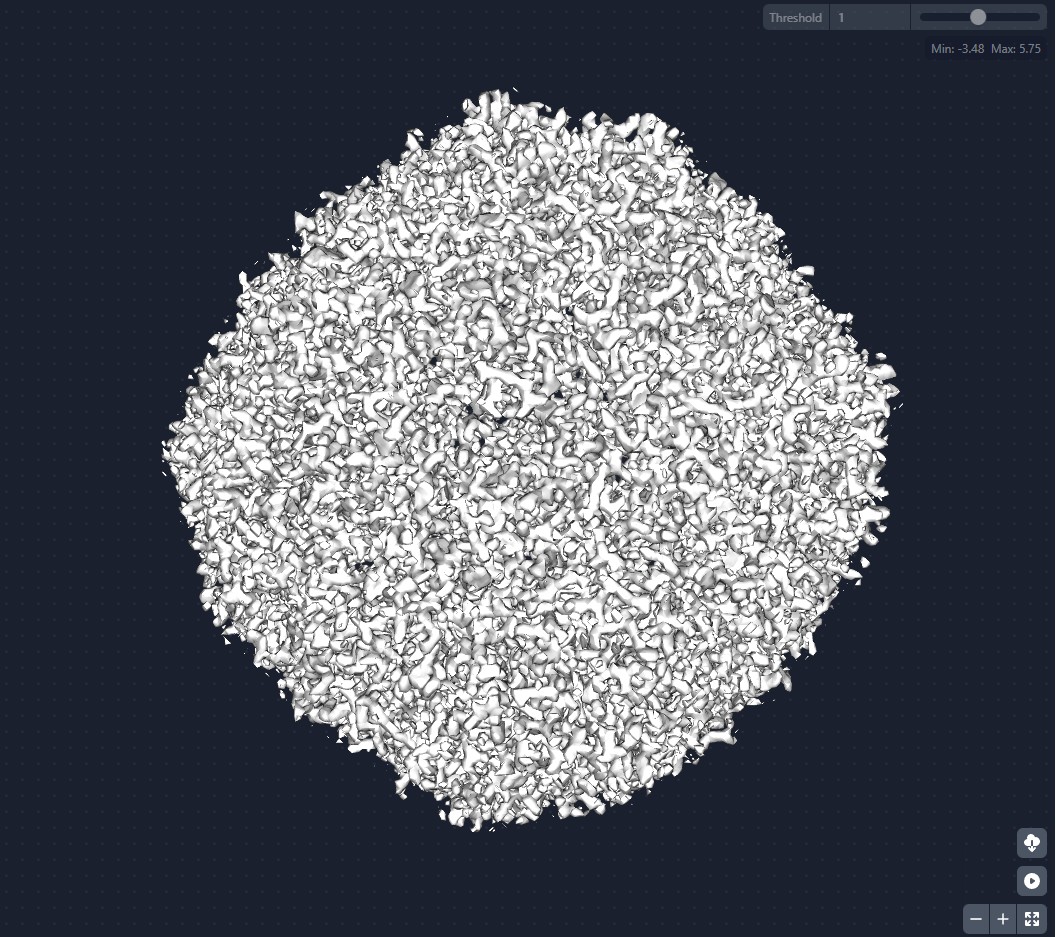

A két új krio-elektronmikroszkóp - a Tundra és a Glacios 2 - elsősorban biológiai molekulák, például fehérjék vagy mikrobák és sejtek szerkezetének vizsgálatára szolgál. A kutatók először az egyik berendezéssel ellenőrzik a minták minőségét, majd a másikkal részletes adatokat gyűjtenek, amelyekből háromdimenziós molekulamodellek készíthetők.

A krio-elektronmikroszkópia különlegessége, hogy a mintákat rendkívül gyorsan, csaknem –196 °C-ra hűtik le. Ez a módszer megakadályozza, hogy a víz jégkristályokat képezzen, így a biomolekulák eredeti szerkezete változatlan marad.

„Olyan, mintha lefagyasztanánk egy pillanatot az életből. A molekulák abban az állapotban maradnak meg, ahogyan a természetben is működnek, így pontosabban megérthetjük a működésüket” – magyarázta a kutató. Ez különösen fontos például vírusok vizsgálatánál. A módszerrel részletesen feltérképezhető egy vírus szerkezete, például az a fehérje, amellyel a sejtekhez kapcsolódik, ilyen kutatások segítették a tudósokat a járvány idején a COVID-19 vírusának megértésében is.

Ha a kutatók pontosan látják egy biomolekula, például fehérje térbeli szerkezetét, könnyebben megérthetik azt is, hogyan kapcsolódnak hozzá más molekulák, például gyógyszerhatóanyagok.